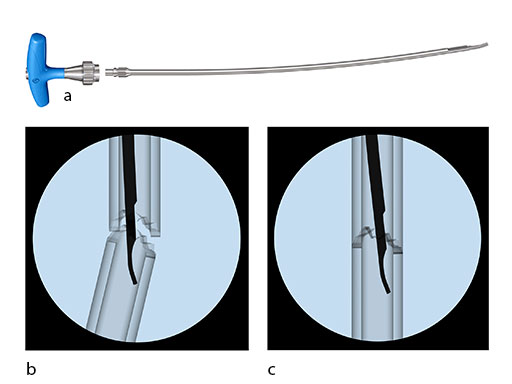

Intramedullary Reduction Tool

Achievement of proper reduction, especially in femoral fractures, can be very challenging. A long reduction tool (Fig 5) has been developed, which has an anatomical curvature and a pointed fingertip to aid in fracture reduction.